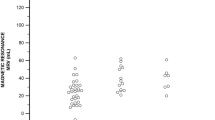

The quantitative approach is based on the determination of the individual RF. This parameter is included in all current recommendations [3, 5, 6]. RF relies on the determination of LVSVtot and LVSVeff. The absolute value of MVRegVol should always be interpreted with respect to LVEDV. It is obvious that the amount of MVRegVol is much more important in small hearts than in larger hearts, which can be impressively illustrated by interspecies comparisons (Fig. 6). In consequence, haemodynamic conditions can be characterized by plausible LVEDV, LVEF, and LV forward stroke volume (= LVSVeff). Determination of MVRegVol by the 2D-PISA method alone was associated with significant overestimation of MRRegVol as documented in recent transcatheter MV repair (TMVR) trials [10, 58, 59] and further MR outcome trials [60].

Illustration of the interspecies differences of regurgitant volume in relation to total stroke volume (LVSVtot). The normal LVSVtot of a rat heart is about 0.5 ml [61] resulting in a regurgitant fraction (RF) of 50% if regurgitant volume at the mitral valve (MVRegVol) is about 0.25 ml. The normal LVSVtot of an elephant heart is about 20 l [62] resulting in a RF of about zero, if MVRegVol is about 0.25 ml. An RF of about 50% needs an MVRegVol of about 5 l